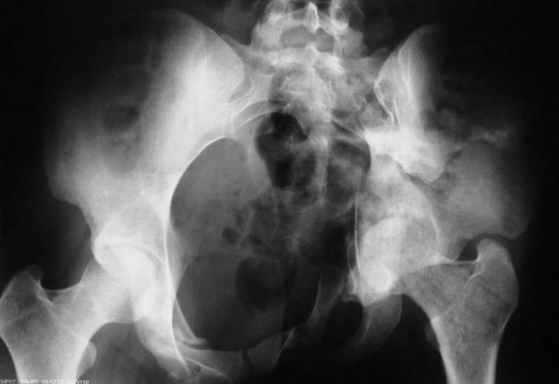

Рентгенограмма до операции

Перелом. Внутритазовый обзор.